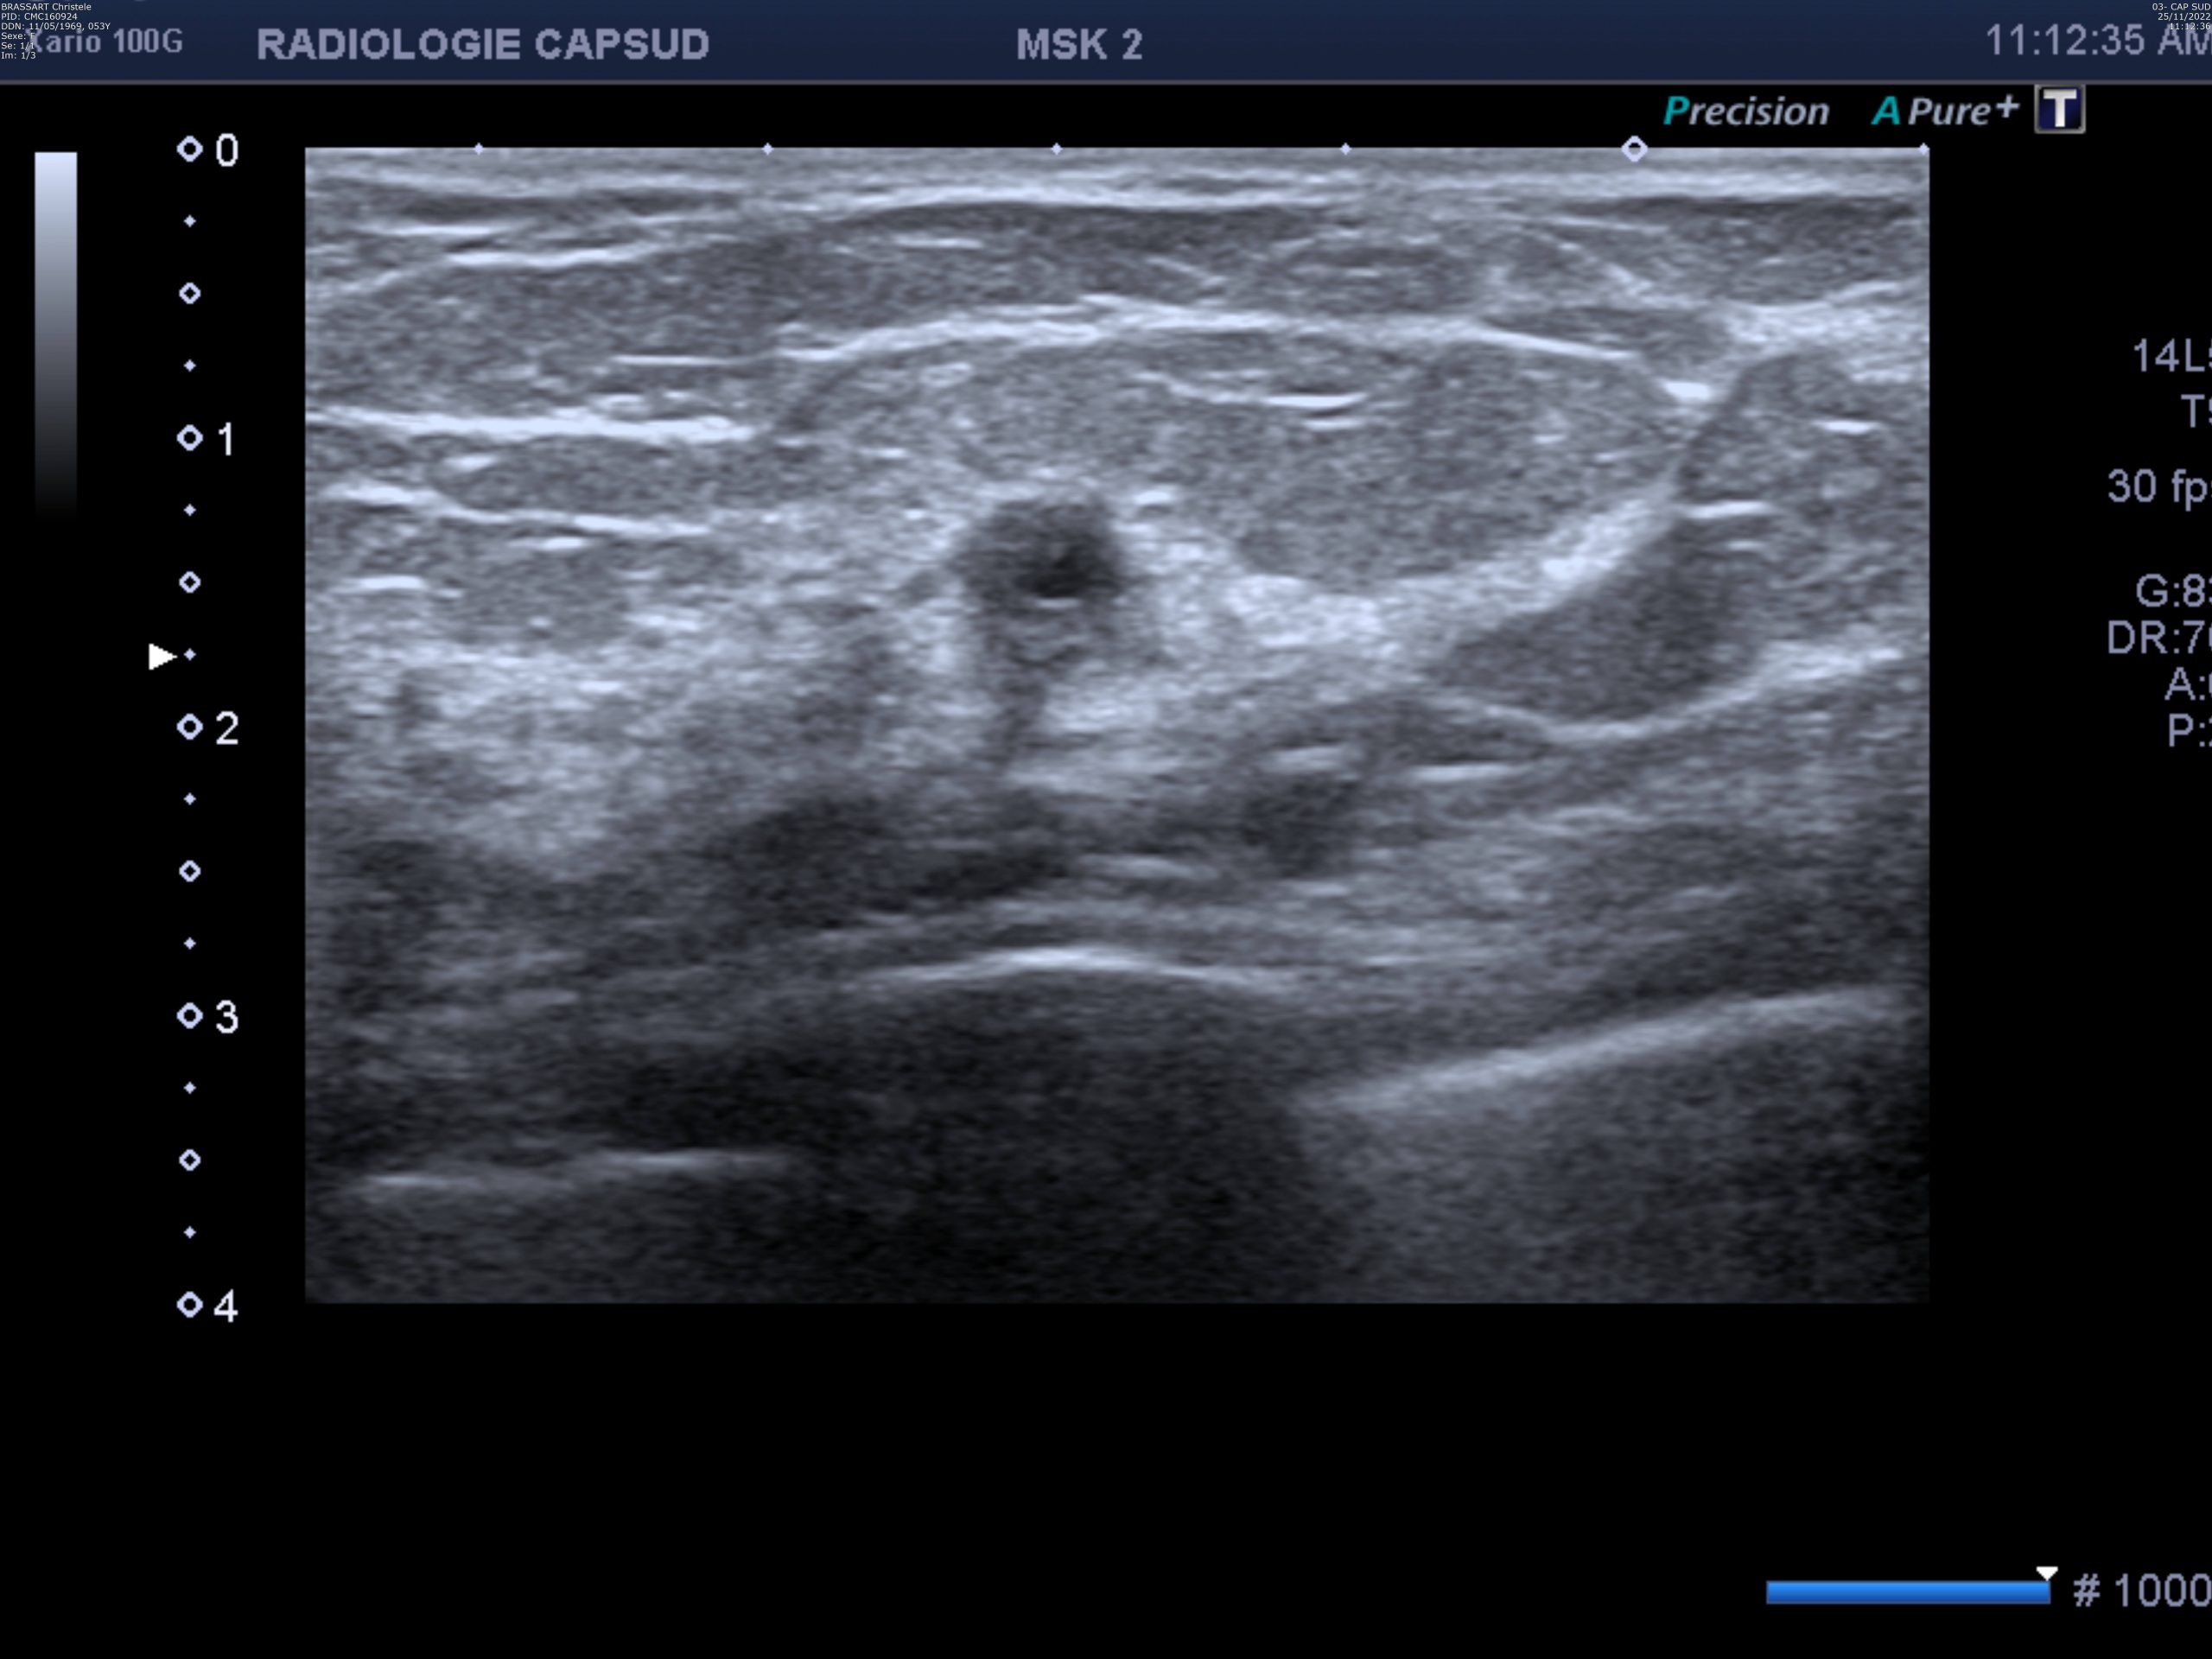

L’échographie confirme une formation hypoéchogène de 8 mm du quadrant externe du sein droit à 6 cm du mamelon à contour polylobé.